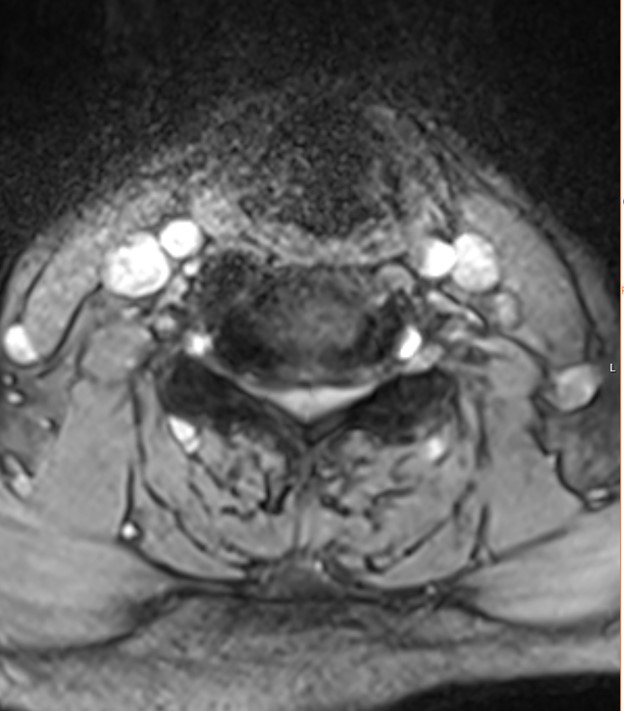

Axial T2-viktad MR-bild mellan C4 och C5 på en 68-årig kvinna med balanssvårigheter, klumpighet och radikulopati mot händerna. I status fanns bilateralt positivt Hoffmanns tecken och stegrade reflexer. I bilden ses en bredbasig diskbuktning och fasettledshypertrofi som försnävar spinalkanalen.